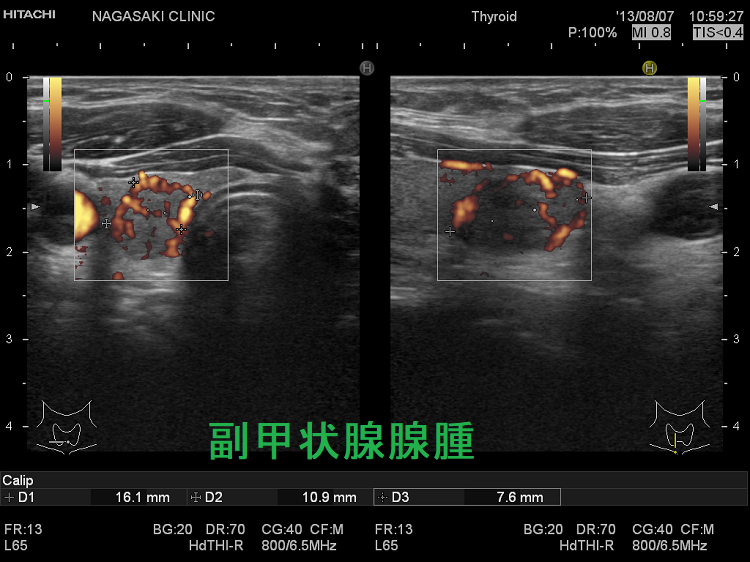

(➸)原因となる副甲状腺腺腫、副甲状腺癌、副甲状腺過形成をデジタルハイビジョン超音波診断装置で診断。エコーでは、甲状腺とのインピーダンスの違いにより、甲状腺-副甲状腺境界部に線状高エコーが生じます(右図の↓)。内部は中心血流を認め、リンパ節でないのが分かります。

ケース①

ケース②